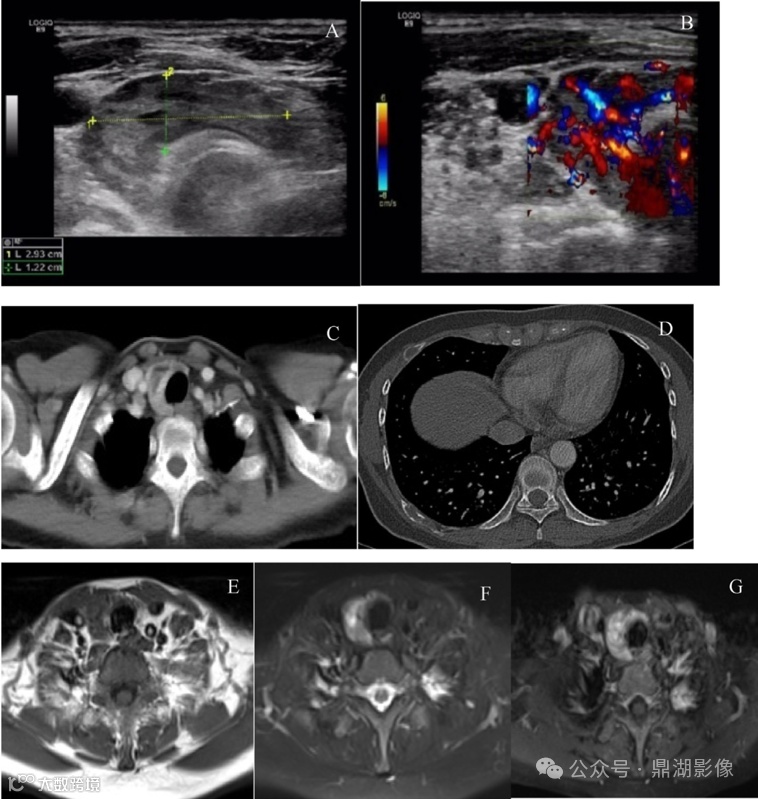

超声(图A-B)显示甲状腺右侧叶和气管之间大小约2.93cm×1.22cm的高回声结节,内部回声不均,其内可见无回声液性暗区。彩色多普勒超声显示血供丰富。

CT(图C-D)显示甲状腺右侧叶旁边见稍低密度结节,强化不均且强化程度低于正常甲状腺组织。

MRI成像(图E-G)显示甲状腺右侧叶新月形结节,T1WI等信号,T2WI呈稍高信号,边界清楚,大小约2.2cm×1.7cm,增强后病灶不均匀强化且强化程度高于正常甲状腺组织。

[¹⁸F]FDG PET-CT(图H-J)显示甲状腺右侧叶大小约2.1cm×1.5cm×2.4cm的低密度结节,未见代谢增高,多个肋骨、多个胸腰椎椎体及双侧髂骨见囊性骨质破坏,边缘清楚,未见硬化边,未见钙化及肿块形成,上述骨质破坏区域代谢不均,SUVmax介于1.0-8.0之间,绝大多数病变表现为低密度改变。

基于以上[¹⁸F]FDG PET-CT 表现,患者初步诊断为多发性骨髓瘤,建议针对右侧髂骨病变穿刺活检;患者甲状腺右侧叶未见代谢增高。

A:超声示低回声肿块;

B:CDFI内部可见丰富的血流信号;

C:CT示稍低密度肿块;

D:CT示肋骨内多发囊性、膨胀性骨质破坏;

E:肿块T1WI呈等信号;

F:肿块T2WI呈稍高信号;

G:肿块MRI呈不均匀强化。

J:甲状旁腺肿块内未见代谢增高,多根肋骨、多个胸腰椎及双侧髂骨见囊性骨质破坏区,破坏区内可见不同程度的放射性摄取增高;